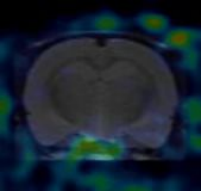

4.實驗動物(wù)的(de)靶器(qì)官及全身(shēn)顯像或模拟臨床功能(néng)測定試驗的(de)研究方法,試驗條件(jiàn)等資料,試驗觀察各時(shí)相(xiànεg)的(de)顯像或功能(néng)測定結果

一(yī)、實驗動物(wù)的(de)全身(shēn)顯像及延遲顯像

實驗動物(wù)為(wèi)小(xiǎo)鼠1隻,由杭州醫(yī)學院提供,體(tǐ)重約200g,雄性,。注射藥物(wù)後麻醉後進行(xíng)PET掃描,采←集圖像,獲得(de)藥物(wù)在體(tǐ)內(nèi)分(fēn)布圖。顯像後實驗動物(wù)逐漸蘇醒,恢複正常,飲食、二便、精神狀态佳。